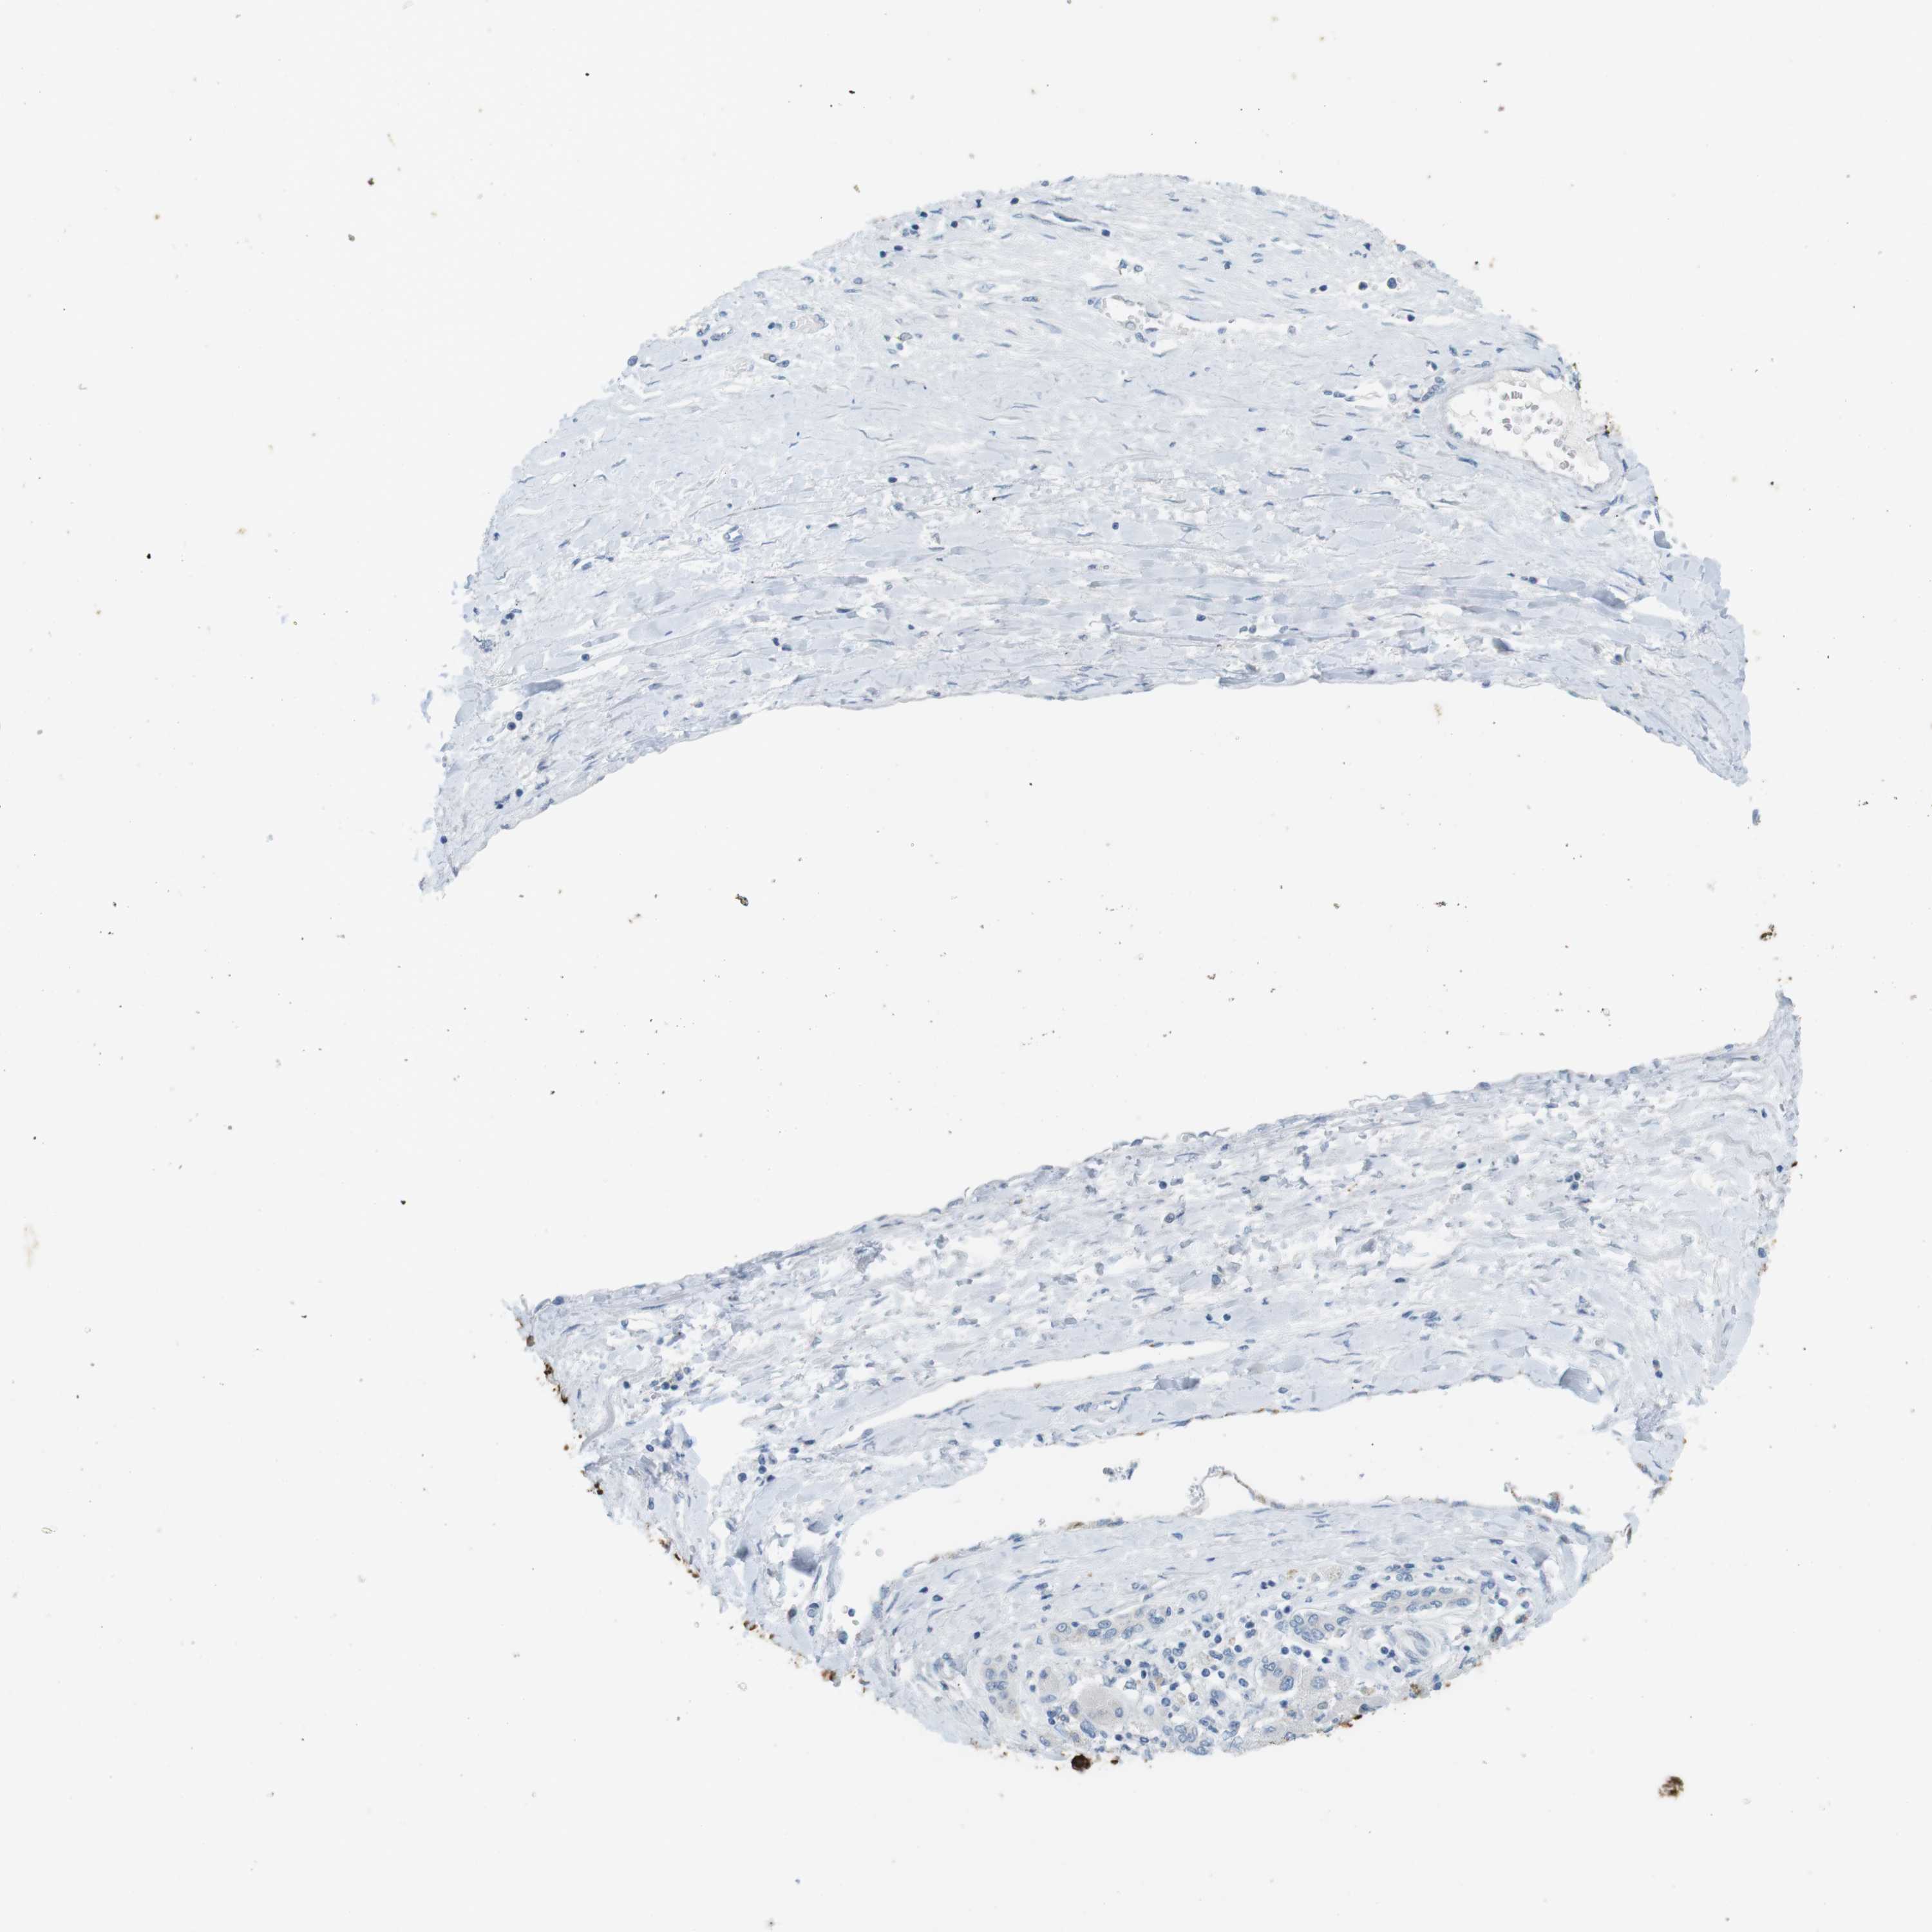

LIVER CANCER - Protein expressioni

A mouse-over function shows sample information and annotation data. Click on an image to view it in a full screen mode. Samples can be filtered based on level of antibody staining by selecting one or several of the following categories: high, medium, low and not detected. The assay and annotation is described here.

Note that samples used for immunohistochemistry by the Human Protein Atlas do not correspond to samples in the TCGA dataset.

Antibody stainingi

Antibody staining in the annotated cell types in the current human tissue is reported as not detected, low, medium, or high, based on conventional immunohistochemistry profiling in selected tissues. This score is based on the combination of the staining intensity and fraction of stained cells.

Each image is clickable and will lead to virtual microscopy that enables deeper exploration of all samples and also displays staining intensity scores, fraction scores and subcellular localization as well as patient and tissue information for each sample.

Antibody HPA008246

Antibody CAB009396